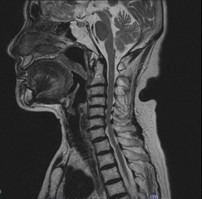

首で多い病気

• 変形性頚椎症

• 頚椎椎間板ヘルニア

• 頚椎症性脊髄症

• 頚椎後縦靭帯骨化症

首から手にかけての痛みやしびれ、手指の巧緻運動障害(細かい動作ができない)、歩行困難、膀胱直腸障害等の症状を伴う、上記のような病気があります。

治療について

受診された際には問診、診察を行い、画像検査(レントゲン、MRI、CT)や採血検査を行い、診断を付け、治療方針を説明します。 上記のような保存治療を行っても取れない痛みや、手の使いにくさや歩行困難、排尿排便障害などが出現し症状が進行性の場合は手術加療が必要となります。

術前